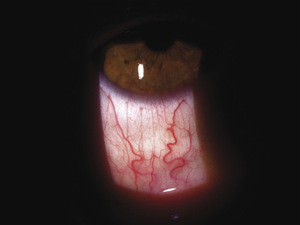

Zapalenie twardówki przednie (ryc. 3) |